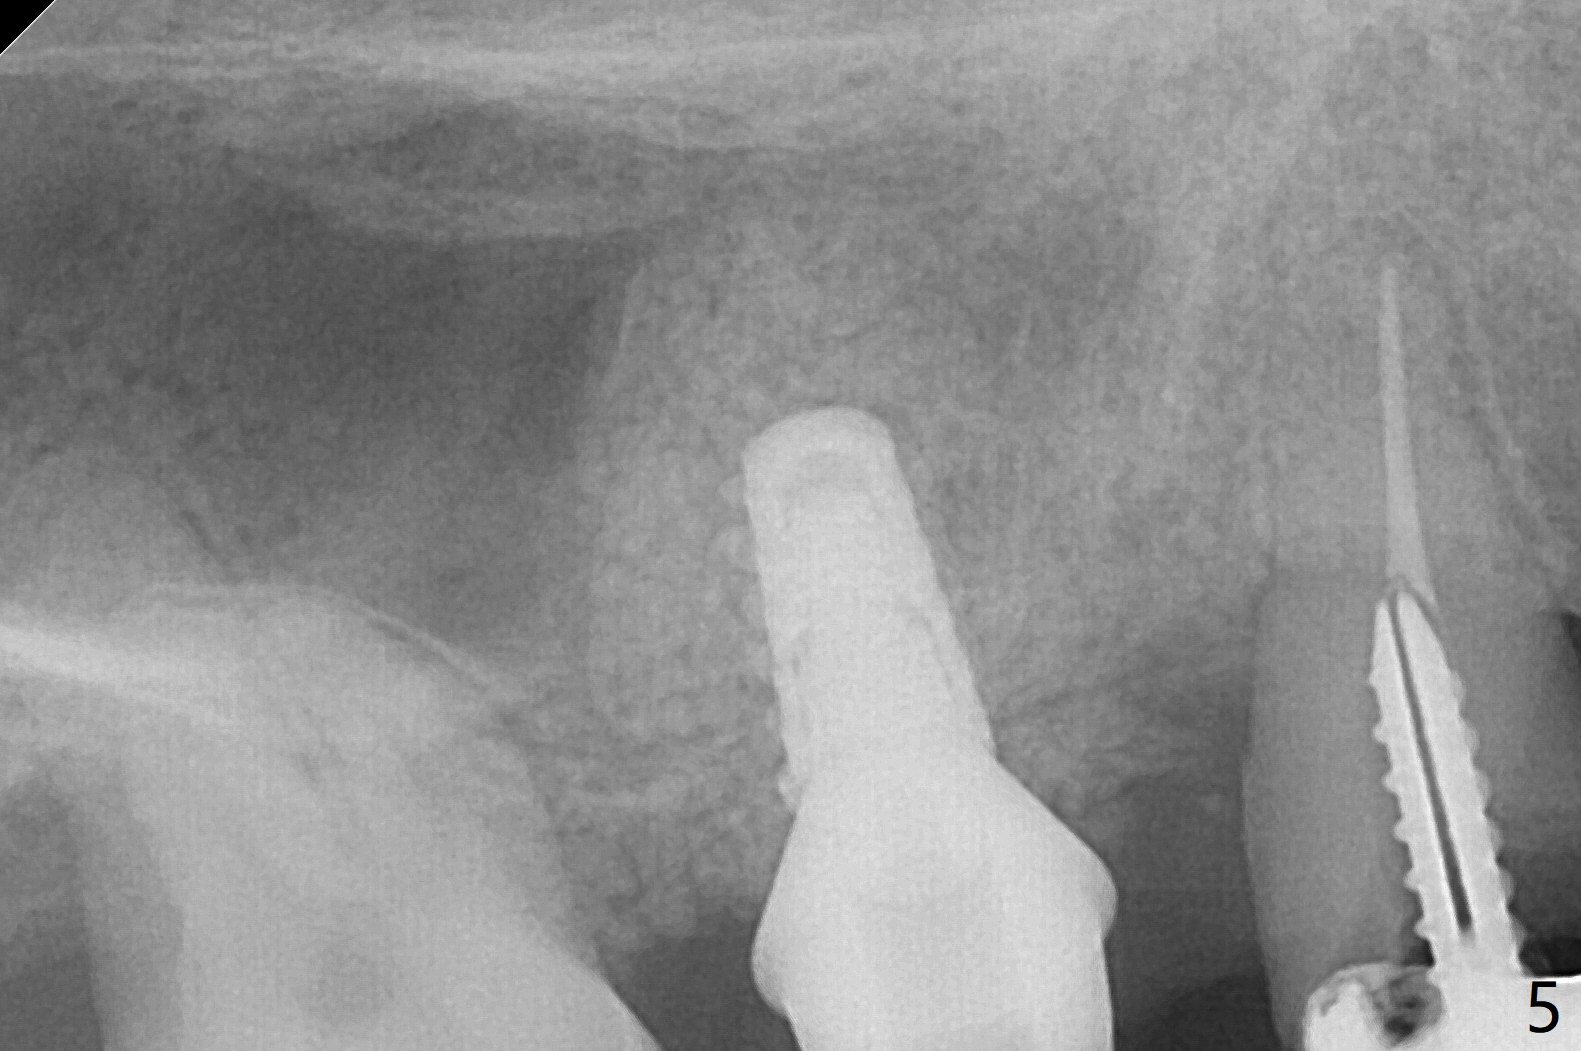

49岁女(个子小)牙齿问题多,同意先做右上5,6种植,6骨质高度1-2毫米,一个月前因动脉出血外提升失败。今天她回来做内提升,同意如果条件合适,同期徒手植牙(将来做一个磨牙牙冠),事先服用阿奇霉素。使用粘性骨粉和报废植体做内提(图一:*),最后植入4x7毫米植体(35Ncm),近中颊侧平牙槽嵴(图二:*),其余骨上 (图三: *),不敢植入太深,怕掉入上颌窦。第二个预防掉入上颌窦措施是利用大号基台(图三),然后在基台周围放置骨粉(图四:*,五),缝合,牙周敷料。伤口愈合后,准备制作树脂敷料,防止植体和基台往口腔脱落。术后五天复诊,无上颌窦炎症,牙周敷料稳定。她再回来时已经术后4.5个月,植体稳定,更换基台没有疼痛(图六,七),口腔卫生极佳,使用水牙线,不敢患侧刷牙。